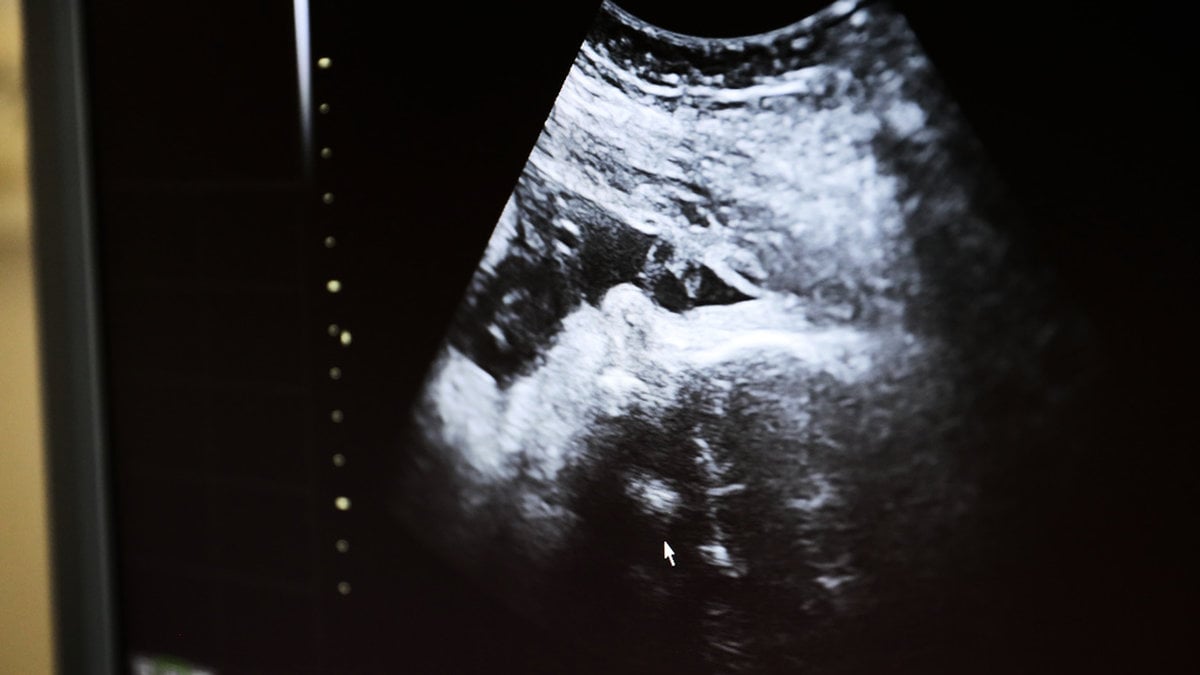

Flera regioner fasar ut fosterdiagnostiktestet kub. Orsaken är nya EU-regler som ska vara införda senast 2028.